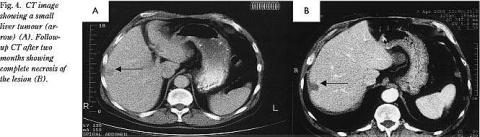

RF-nålen kan indføres UL-vejledt i tumoren perkutant, vha. laparoskop eller ved åben kirurgi. Den perkutane behandling foretages i generel anæstesi. Hver ablation af et 4-5 cm i diameter stort vævsområde tager 10-30 minutter. Når RF-nålen retraheres øges strømstyrken, så nålestikkanalen koaguleres for at undgå udsæd af tumorceller. Den perkutane teknik anvendes ved tumorer, der er op til 4 cm i diameter og er lokaliseret, så RF-nålen UL-vejledt kan indføres i tumoren (Fig. 2, Fig. 3 ). Større tumorer kræver derfor flere overlappende nåleapplikationer. Laparoskopisk RF-behandling anvendes nu ved overfladisk beliggende tumorer, som kan være vanskelige at erkende tilstrækkeligt godt visuelt ved perkutan UL-scanning (Fig. 4 ). Åben RF-behandling udføres evt. samtidig med resektion af resecerbare tumorer, hvor ikkeresecerbare tumorer RF-behandles. Man kan da samtidig foretage inflow -okklusion af levergennemblødningen med tang på ligamentum hepatoduodenale (Pringles manøvre). Herved kan kølevirkningen af levergennemblødningen mindskes, så et større tumorrumfang kan opvarmes og destrueres. Samtidig kan tumorer, der er tæt på større blodkar, specielt v. portae og v. hepatica, bedre behandles.

Efter fem uger foretages der CT og efter seks uger UL-scanning for at bedømme effekten af RF-behandlingen (Fig. 4). Der tages UL-vejledt biopsi fra randzonen af det RF-behandlede område for at se, om der resterer levende tumorvæv. Hvis der ikke resterer levende tumorvæv foretages UL-scanning hver tredje måned det første år og siden hver sjette måned. Hvis nye tumorer diagnosticeres, foretages der fornyet RF-behandling, hvis ovennævnte indikationer stadig er opfyldt.